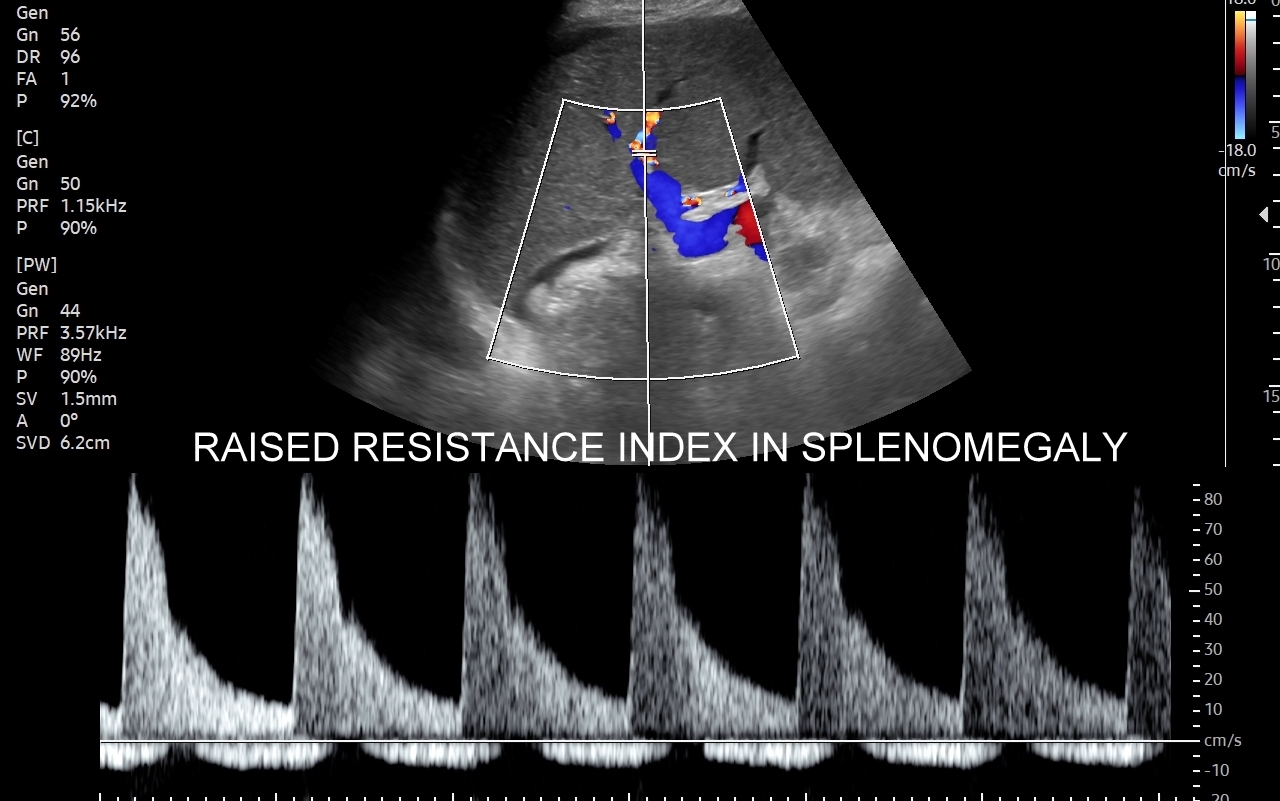

Rozwinięciem standardowego badania USG jamy brzusznej jest badanie multiparametryczne MPUS (ang. multiparametric ultrasound), w ramach którego wykorzystuje się różnorodne, nowoczesne modalności sonograficzne, takie jak tryby mikrounaczynienia MVI, B-flow, elastografię, ilościową ocenę stłuszczenia wątroby QUS, czy tryb Dopplera spektralnego, a to wszystko w celu uzyskania dodatkowej oceny funkcjonalnej i biologicznej struktur, narządów oraz tkanek jamy brzusznej. Obrazowanie MPUS niejednokrotnie poprawia także wizualną ocenę narządów wewnętrznych, czego przykładem jest zastosowanie trybu MVI w ramach bezkontrastowej angiografii sonograficznej naczyń oraz w ocenie guzów nerek. Klasycznymi i najczęstszymi zastosowaniami badania MPUS są jednakże funkcjonalna ocena wątroby w kierunku stłuszczenia, zwłóknienia, zapalenia i nadciśnienia wrotnego, a także ocena żywotności i funkcji nerek.